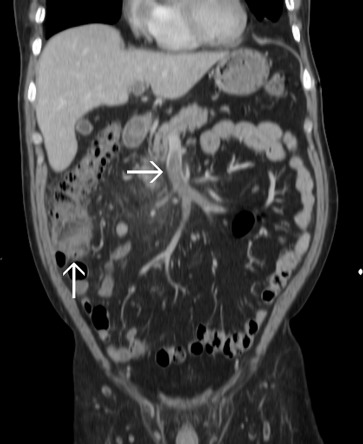

A 60-year-old man was hospitalized because of acute diverticulitis complicated with Bacteroides fragilis bacteremia. The computed tomography (CT) scan showed cecal diverticulitis with superior mesenteric vein (SMV) thrombosis ( Fig. 1 ). At that time, he received parenteral antibiotics for 2 weeks and then oral antibiotics for 1 week after discharge. Nine days later, he presented to our emergency department with progressive abdominal pain and fever. CT scan demonstrated improved diverticulitis but progressive local peritoneal inflammation around the SMV thrombosis (Fig. 2 ).

Figure 2.

The upward arrow indicates the improved diverticulitis and the rightward arrow indicates the progressive thrombophlebitis.